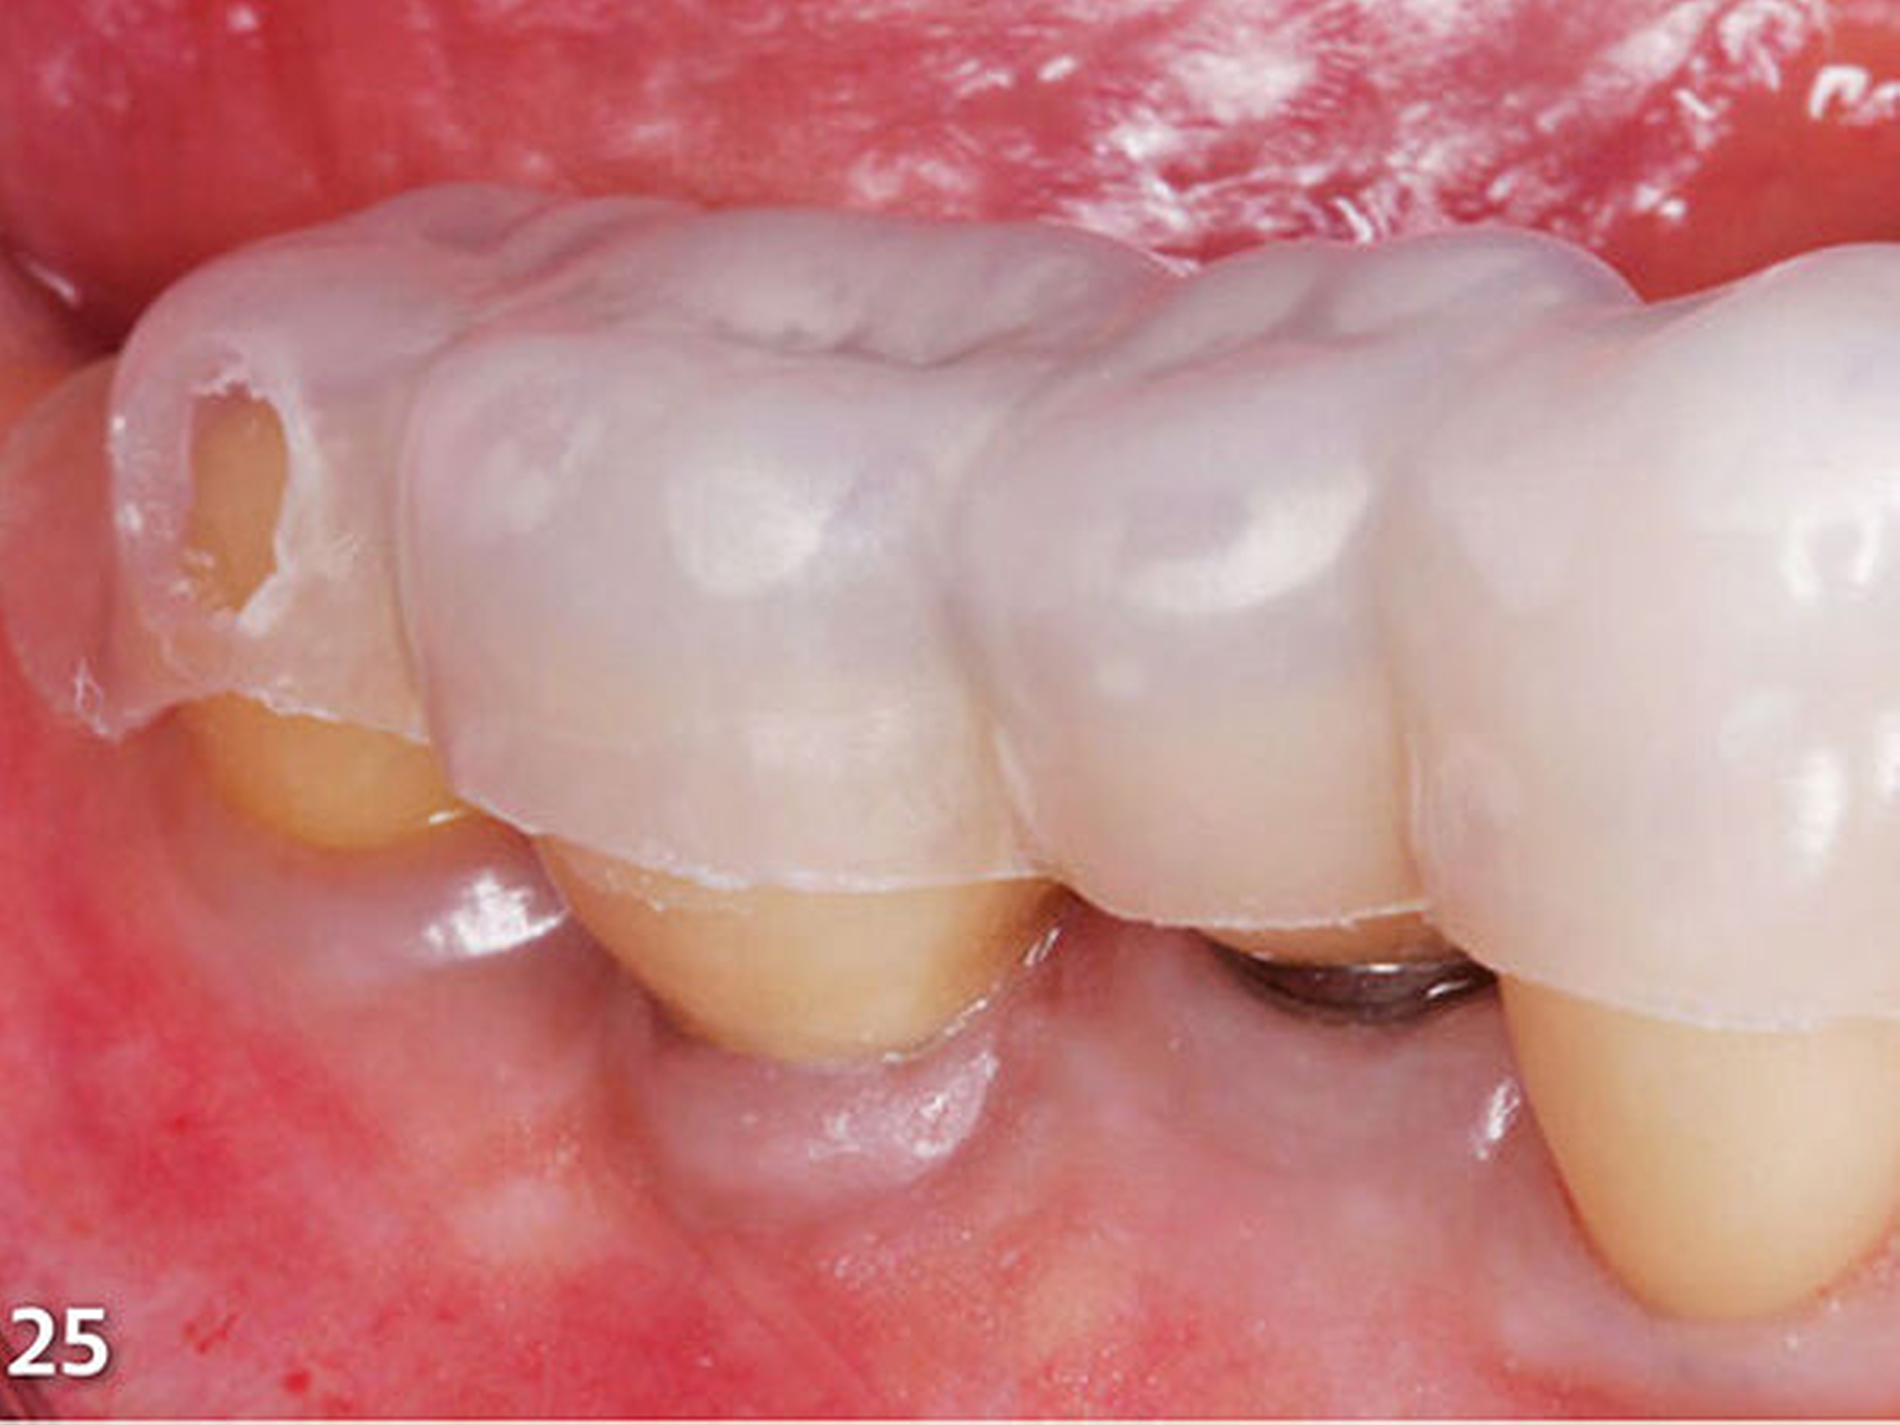

Nach dem bündigen Verschleifen der bukkalen und oralen Einspritz- und Entlüftungskanäle wurde die zweite Übertragungsschiene (Schiene 2), die ebenfalls im Frontbereich geteilt wurde, eingebracht, nachdem der damit zu rekonstruierende endständige Molar zuvor silikatisiert, silanisiert und mit Adhäsiv vorbehandelt worden war (Abb.25). Die Abstützung dieser Schablone erfolgte an den gerade zuvor im ersten Schritt aufgebauten, anterior liegenden Seitenzähnen. Der Aufbau der Kaufläche wurde wieder nach der zuvor beschriebenen Methode ausgeführt (Abb.26).

Analog erfolgte der Aufbau der Seitenzahnkauflächen der anderen Kieferhälfte ebenfalls in zwei Schritten (Abb.27). Durch den Aufbau aller Seitenzähne des Unterkiefers ist die temporäre Bisshebung bereits weitgehend abgeschlossen (Abb.28). Mit der dritten Übertragungsschiene (Schiene 3) (Abb.29) wurden die Unterkieferfrontzähne nach Ätzung der Zahnhartsubstanzen mit Phosphorsäure und nachfolgender adhäsiver Vorbehandlung inzisal aufgebaut (Abb.30).